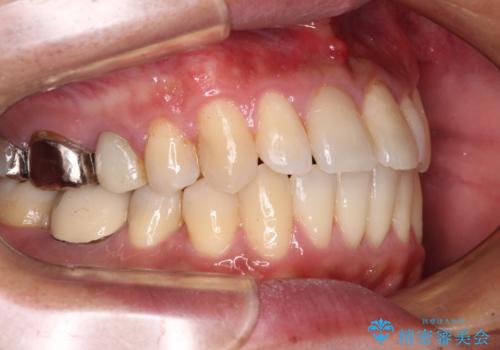

受け口傾向の咬み合わせ 前歯のデコボコをワイヤー矯正で素早く改善

前歯のクロスバイトは、改善の途中で歯髄壊死を起こすリスクが高くなるため、マウスピース矯正よりもワイヤー矯正をお勧めしております。

この患者様もクロスバイトはあっという間に改善され、1年強で速やかに治療を終えることができました。